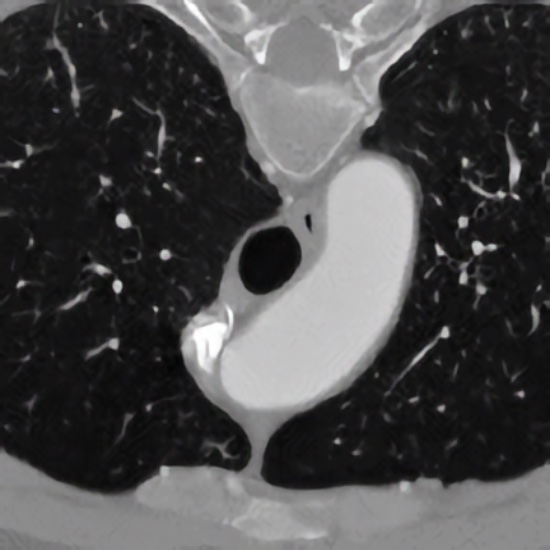

Development of model-based approaches for accurate quantification of the 3D morphology of human blood vessels from 3D tomographic images (e.g., 3D CTA, 3D MRA). The approaches combine 3D cylindrical intensity models with incremental model fitting. The main application domain is the quantification of the aortic arch and its main bifurcating branches for improved operation planning using stent grafts.

Model-Based Segmentation and Motion Analysis of the Thoracic Aorta from 4D ECG-Gated CTA Images

Biesdorf A, Wörz S, Müller T, Weber TF, Heye T, Hosch W, von Tengg-Kobligk H, and Rohr K

Proc. 14th Internat. Conf. on Medical Image Computing and Computer-Assisted Intervention (MICCAI'2011)